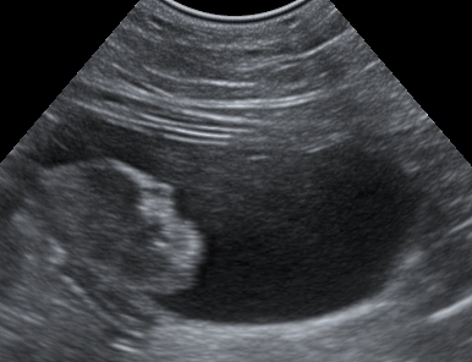

Sowohl eine Blasenentzündung als auch gut- oder bösartige Tumoren der Harnblase können beim Hund zu ähnlichen klinischen Symptomen führen, wie zum Beispiel zu blutigem Urin, Harnabsatzproblemen oder Inkontinenz. Nach der allgemeinen und speziellen klinischen Untersuchung kann die Harnblase mittels Ultraschall genauer angeschaut werden, um mögliche Tumoren zu identizieren. Zur weiteren Diagnostik kann je nach Lage des Falles eine Laboruntersuchung des Urins auf das Vorhandensein von Bakterien, Kristallen oder Tumorzellen notwendig sein.

Die Methode ist daher vor allem sinnvoll, wenn andere Verfahren keine eindeutige Diagnose liefern oder nur Urin für die Untersuchung zur Verfügung steht. Der Vorteil für den Patienten ist, dass zunächst Urin(sediment) untersucht werden kann, ohne dass ein invasives Verfahren wie eine Ansaug- oder Exzisionsbiopsie nötig ist. Eine spätere Ultraschalluntersuchung oder eine Endoskopie ist dann aber sowohl bei einem positiven als auch bei einem negativen molekulargenetischen Ergebnis notwendig, um im positiven Fall den Tumor genauer zu charakterisieren bzw. einen falsch negativen Befund auszuschließen.